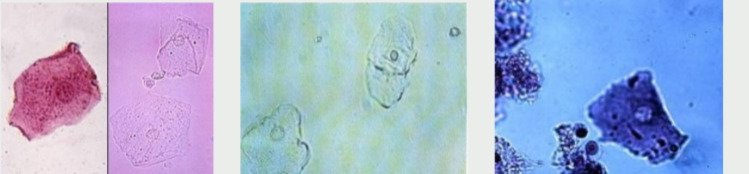

transitional epithelial cell

where are the transitional epithelial cells located

Bladder, ureters, renal pelvis, proximal urethra

squamous epithelial cell

what do squamous epithelial cells line

Distal urethra, vagina, vulva, prepuce

Squamous epithelial cells

Transitional epithelial cells